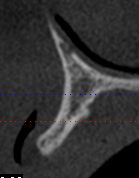

Coupe xray transversale omynvk - Eugenol

Coupe xray transversale greffe m05aen - Eugenol

Coupe xray transversale greffe2 njaaal - Eugenol